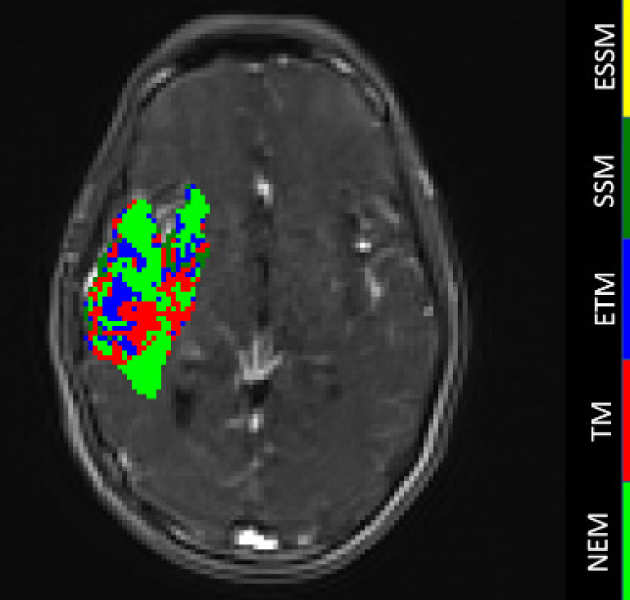

We are developing new machine learning tools to aid clinicians in diagnosing brain tumours through MRI and digital pathology.

We are investigating the integration of different imaging (DCE-MRI, DWI-MRI, DSC-MRI and PET) techniques for the characterization of tumour tissue.